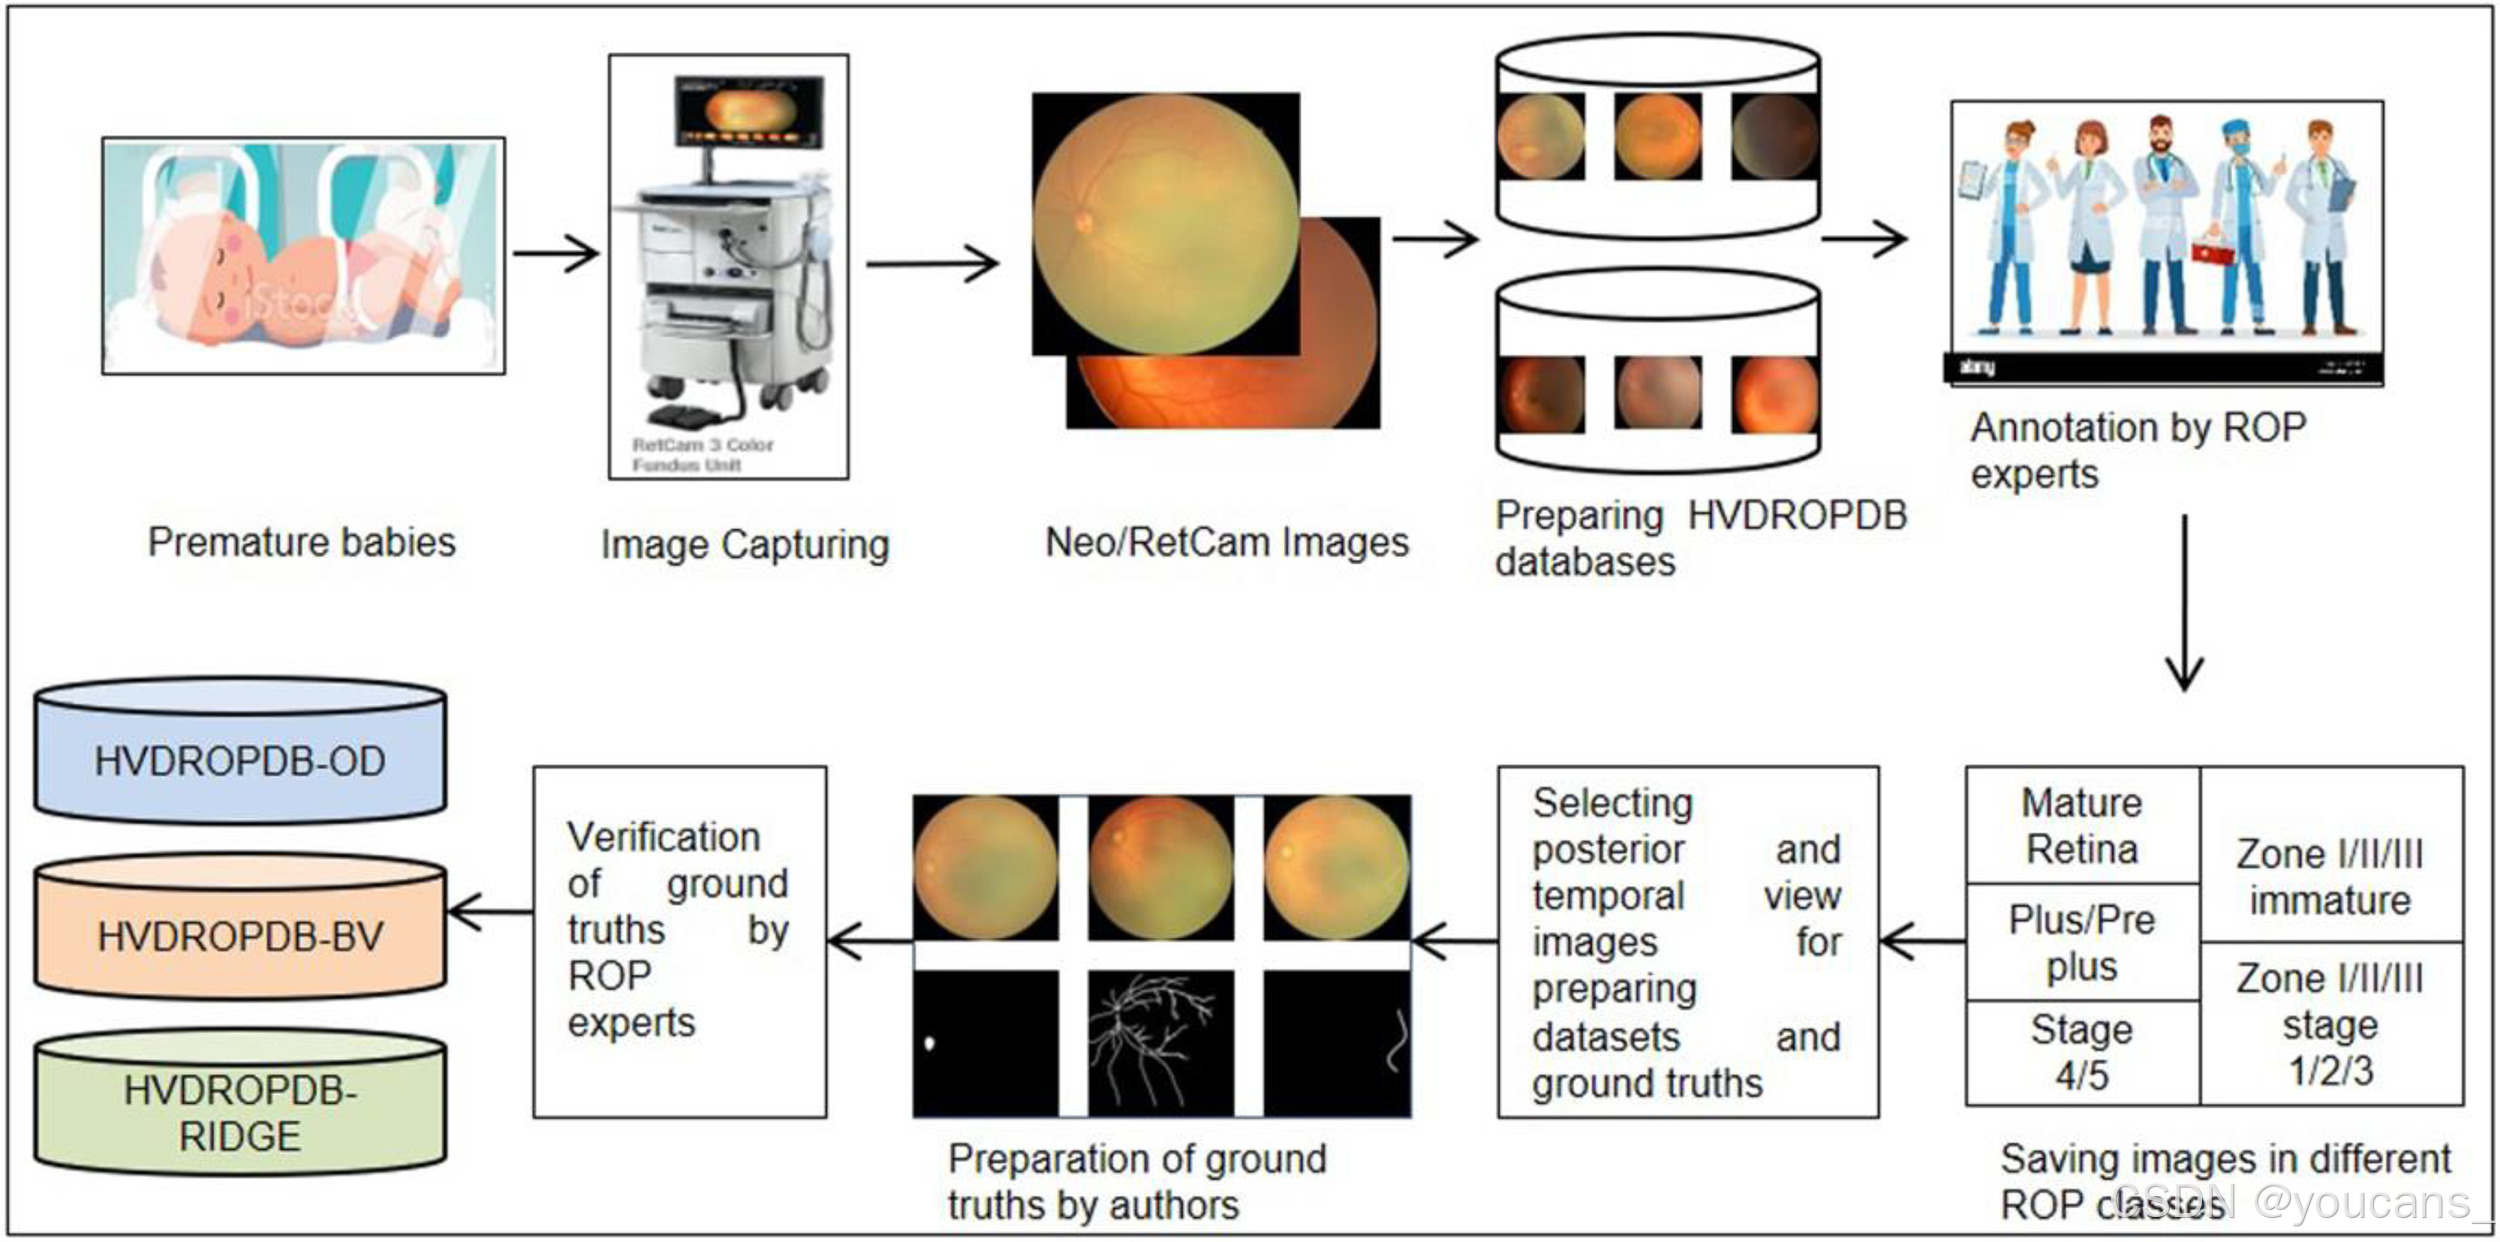

HVDROPDB 是第一个公开发表的用于早产儿眼底图像视网膜结构分割的数据集。该数据集由ROP专家组 标注,并手动标注了地面真相(Ground Truth),以帮助研究人员开发可解释的自动筛查系统。

HVDROPDB 是第一个公开发表的用于早产儿眼底图像视网膜结构分割的数据集,由两种不同的印度人群成像系统收集。该数据集主要用于视网膜图像中的病变分割,并由 ROP专家组 标注。每个数据集都包含早产儿的视网膜眼底图像,并手动标注了掩模图像(Ground Truth),以帮助研究人员开发可解释的自动筛查系统。

该数据集提供了由 RetCam 和 Neo 两种成像系统采集的早产儿的视网膜图像,并进行了标注。眼底图像的 ground truths(masks)(标注的真值/掩模)是使用 Adobe Photoshop 手动制作的,用于分割视盘(Optic Disc)、血管(Vessels)和脊线/分界线(Demarcation Line/Ridge)。研究人员可以使用这些图像和手动标注的分割数据,来分割视网膜结构,检测分区(Zone)和分期(Stage) ,并开发可解释的自动ROP筛查系统。

HVDROPDB数据集由早产儿的后部视图和颞部视图的眼底图像组成,如图1 和图2 所示。图1a 和2a 显示了视网膜后部图像(从视网膜的后方拍摄的图像),图1b 和2b 显示了视网膜颞部图像(从视网膜的侧面拍摄的图像)。

HVDROPDB 以印度浦那的 H.V. Desai 眼科医院命名,该医院负责收集早产儿的眼底图像。这些图像由 RetCam(Clarity MSI,美国)和 Neo(Forus Healthcare,印度)成像系统捕获,如图3所示。RetCam 在全球范围内使用;Neo 的价格合理、便于携带,在印度非常受欢迎。RetCam 和 Neo 图像在数据集中会被单独提供。

数据集准备过程如图7所示。

数据集的图像由位于浦那(Pune )的 PBMA H.V.Desai 眼科医院提供,拍摄于2009年至2022年。受试者是医院筛查ROP的早产儿。这些图像是由训练有素的验光师使用两台具有

120o视场(FOV)的 Neo 或 Retcam 相机拍摄的。

将后视图和颞部视图图像保存在数据库中。在一位有25年经验的高级ROP专家的指导下,由一组具有 5年以上经验的 ROP 专家团队对图像进行标注。在进行标注之前,进行了 观察者间变异性测试,其 Kappa 值为 0.92。然而,由于没有外部专家参与标注,因此不能排除主观偏见的可能性。

这些图像在HVDROPDB数据集中保存为不同的ROP类别。

图7:数据集的准备过程。

所有采集的早产婴儿眼底图像被汇总并存储在一个数据库中。

这些图像由一组在远程医疗模型的ROP图像分级方面经验丰富的医学专家进行标注。为了确保标注过程统一,每个专家都经过培训,以规范注释过程。标注过程中,每位专家每周用 2小时的时间来进行图像标注,确保高效的标注进度。

作者与ROP专家根据现有的文献对标注过程进行了讨论和分析,确保标注规则与行业标准一致。由于时间视图和后视图的图像足以进行诊断,团队决定为每只眼睛选择包含这两种视角的图像进行标注。

我们排除了激光治疗的婴儿和视网膜脱离(ROP并发症)的图像,以避免影响标注的准确性。

RetCam和Neo设备分别提供了不同的图像数据,约1900 张RetCam图像和1100张Neo图像被分别存储在RetCam和Neo数据库中。

在标注过程中,正常图像的数量远高于ROP图像,这有助于平衡数据集的类别分布。

为了使数据集更加具有鲁棒性,我们没有删除质量差的图像。

由于标注分割掩膜图像(Ground Truth)的工作非常复杂,我们目前只提供了部分图像,我们的研究和数据收集仍在进行中。

ROP专家团队根据图像中的病变、正常结构和视网膜的不同象限来分配每个图像的参考诊断。通过这些标准,专家可以对ROP的不同阶段和类型做出准确的分类。

在图像标注过程中,ROP专家团队成员会对图像进行诊断。每个图像的诊断过程会被详细说明。如果团队成员之间对评估存在差异时,由高级 ROP专家进行纠正或确认。

根据《早产儿视网膜病国际分类法》(ICROP),每一对图像(颞视图和后视图)都会被分类为以下几种情况,其中一些图像如图8所示。